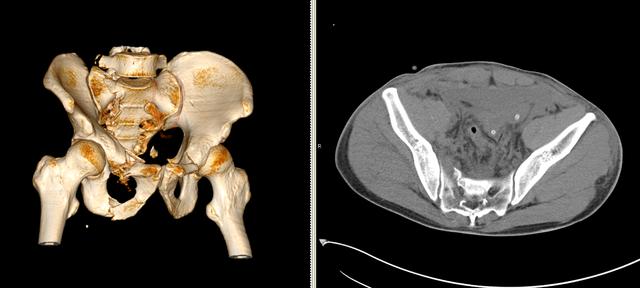

15分鐘后筆者在ICU看到了患者。該患者騎摩托車時(shí)發(fā)生交通事故后摔倒,腰骶部著地,當(dāng)即感骨盆部及腰背部劇烈疼痛,為持續(xù)性劇烈脹痛,會(huì)陰部及右下肢麻木不適,不能站立及行走。被緊急送到解放軍第306醫(yī)院急診時(shí)已處于失血性休克失代償期,患者經(jīng)抗休克治療后生命體征逐漸平穩(wěn),急診以“失血性休克,骨盆骨折,尿道損傷,膀胱造瘺術(shù)后”收住ICU。

次日午間患者無明顯誘因出現(xiàn)大出血,血色素下降到60g/L。ICU、泌尿外科、骨科等專家緊急會(huì)診,一致決定立即行介入止血手術(shù)。